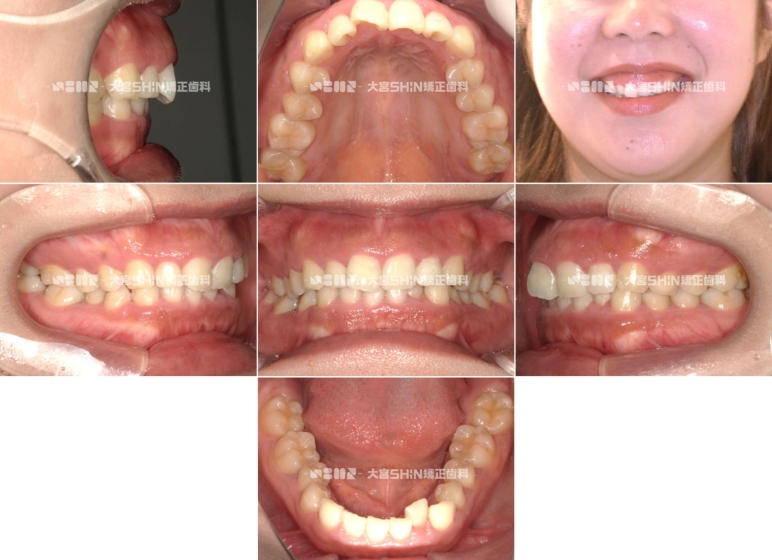

Before

After